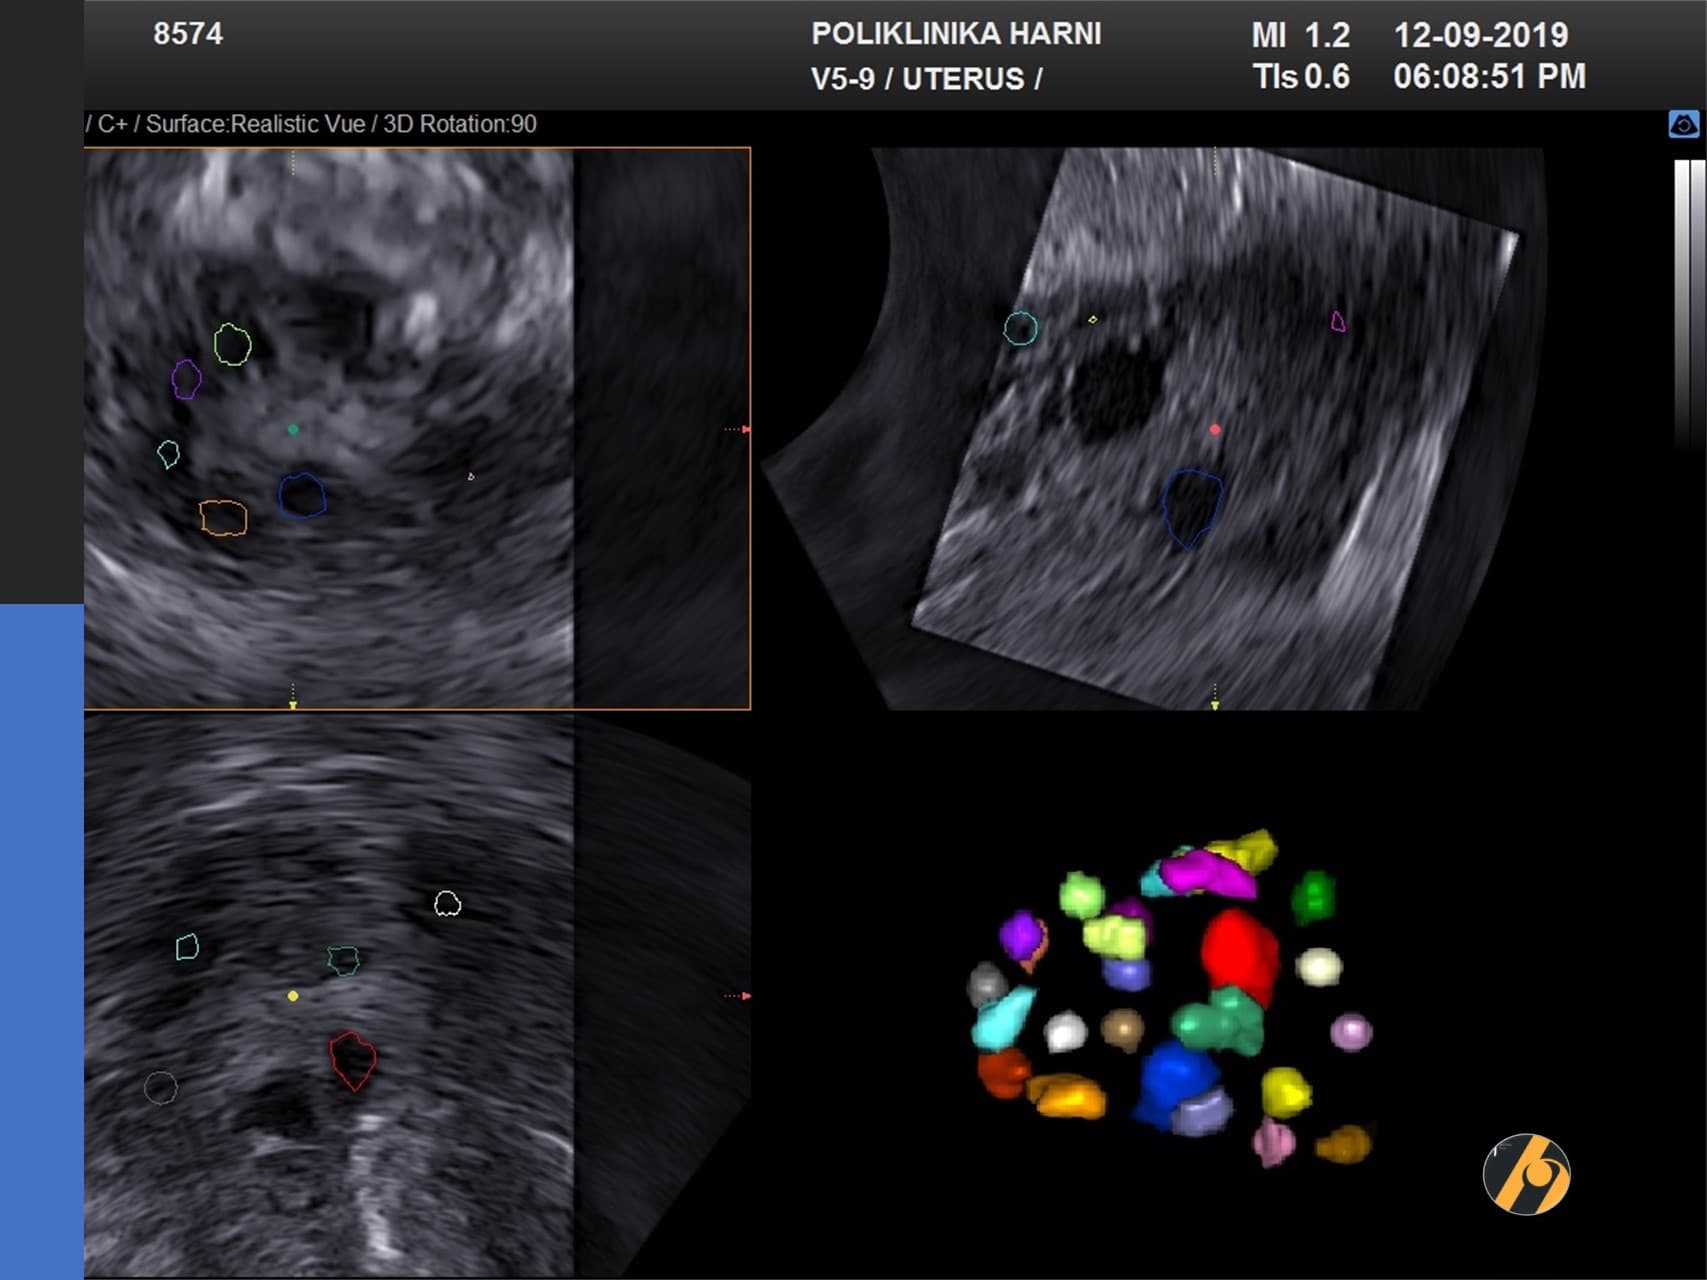

Premda su kardinalna obilježja ovog sindroma hiperandrogenizam i policističan izgled jajnika, niti jedan od pojedinačnih kriterija nije dovoljan da bi se postavila dijagnoza sindroma policističnih jajnika. Osnovna metoda u dijagnostici PCOS je ultrazvučni pregled. Koristi se transvaginalni ultrazvuk, prilikom čega se procjenjuje jesu li povećani jajnici, je li stroma - unutarnji dio jajnika koji proizvodi hormone, zadebljana, postoje li veliki broj folikula koji često tvore sliku ogrlice od perli ako su smješteni periferno ili stvaraju dojam mikrocističnosti kod difuznog rasporeda.

Dijagnoza PCOS prema Rotterdamskim kriterijima postavlja se kada žena ima najmanje dvije od sljedeće tri manifestacije: neredoviti menstrualni ciklusi ili anovulacija, povišena razina muških spolnih hormona i/ili jajnici čiji je volumen veći od 10 ml s najmanje 12 folikula na jednoj zamrznutom ultrazvučnoj slici jajnika. Nužno je isključiti ostala stanja sa sličnim znacima kao što su tumori koji stvaraju muške spolne hormone ili Cushingova bolest. Jajnici koji imaju policističan izgleda, s normalnom funkcijom i bez povišene razine muških spolnih hormona ne spadaju u sindrom policističnih jajnika i ne treba ih kao takve liječiti.

Uz ultrazvuk se u postavljanju dijagnoze PCOS koristi i niz drugih pretraga kao što su mjerenje protoka krvi kroz jajnike (kolor Dopler), određivanje bazalnog hormonskog statusauz analizu metabolizma – određivanje inzulinske rezistencije praćenjem razine glukoze i inzulina i testa opterećenja šećerom - OGTT, analiza učinkovitosti inzulina, mjerenje količine i rasporeda masnog tkiva i druge pretrage, ovisno o vodećim simptomima.